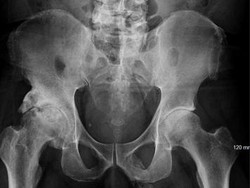

Kondisi Gaza Memprihatinkan! WHO: Butuh 5-10 Tahun Selamatkan Semua Pasien Kritis

WHO mendesak percepatan evakuasi medis di Gaza, mengingat butuh 5-10 tahun untuk berhasil mengevakuasi seluruh korban bila kondisinya terus terjadi seperti ini.